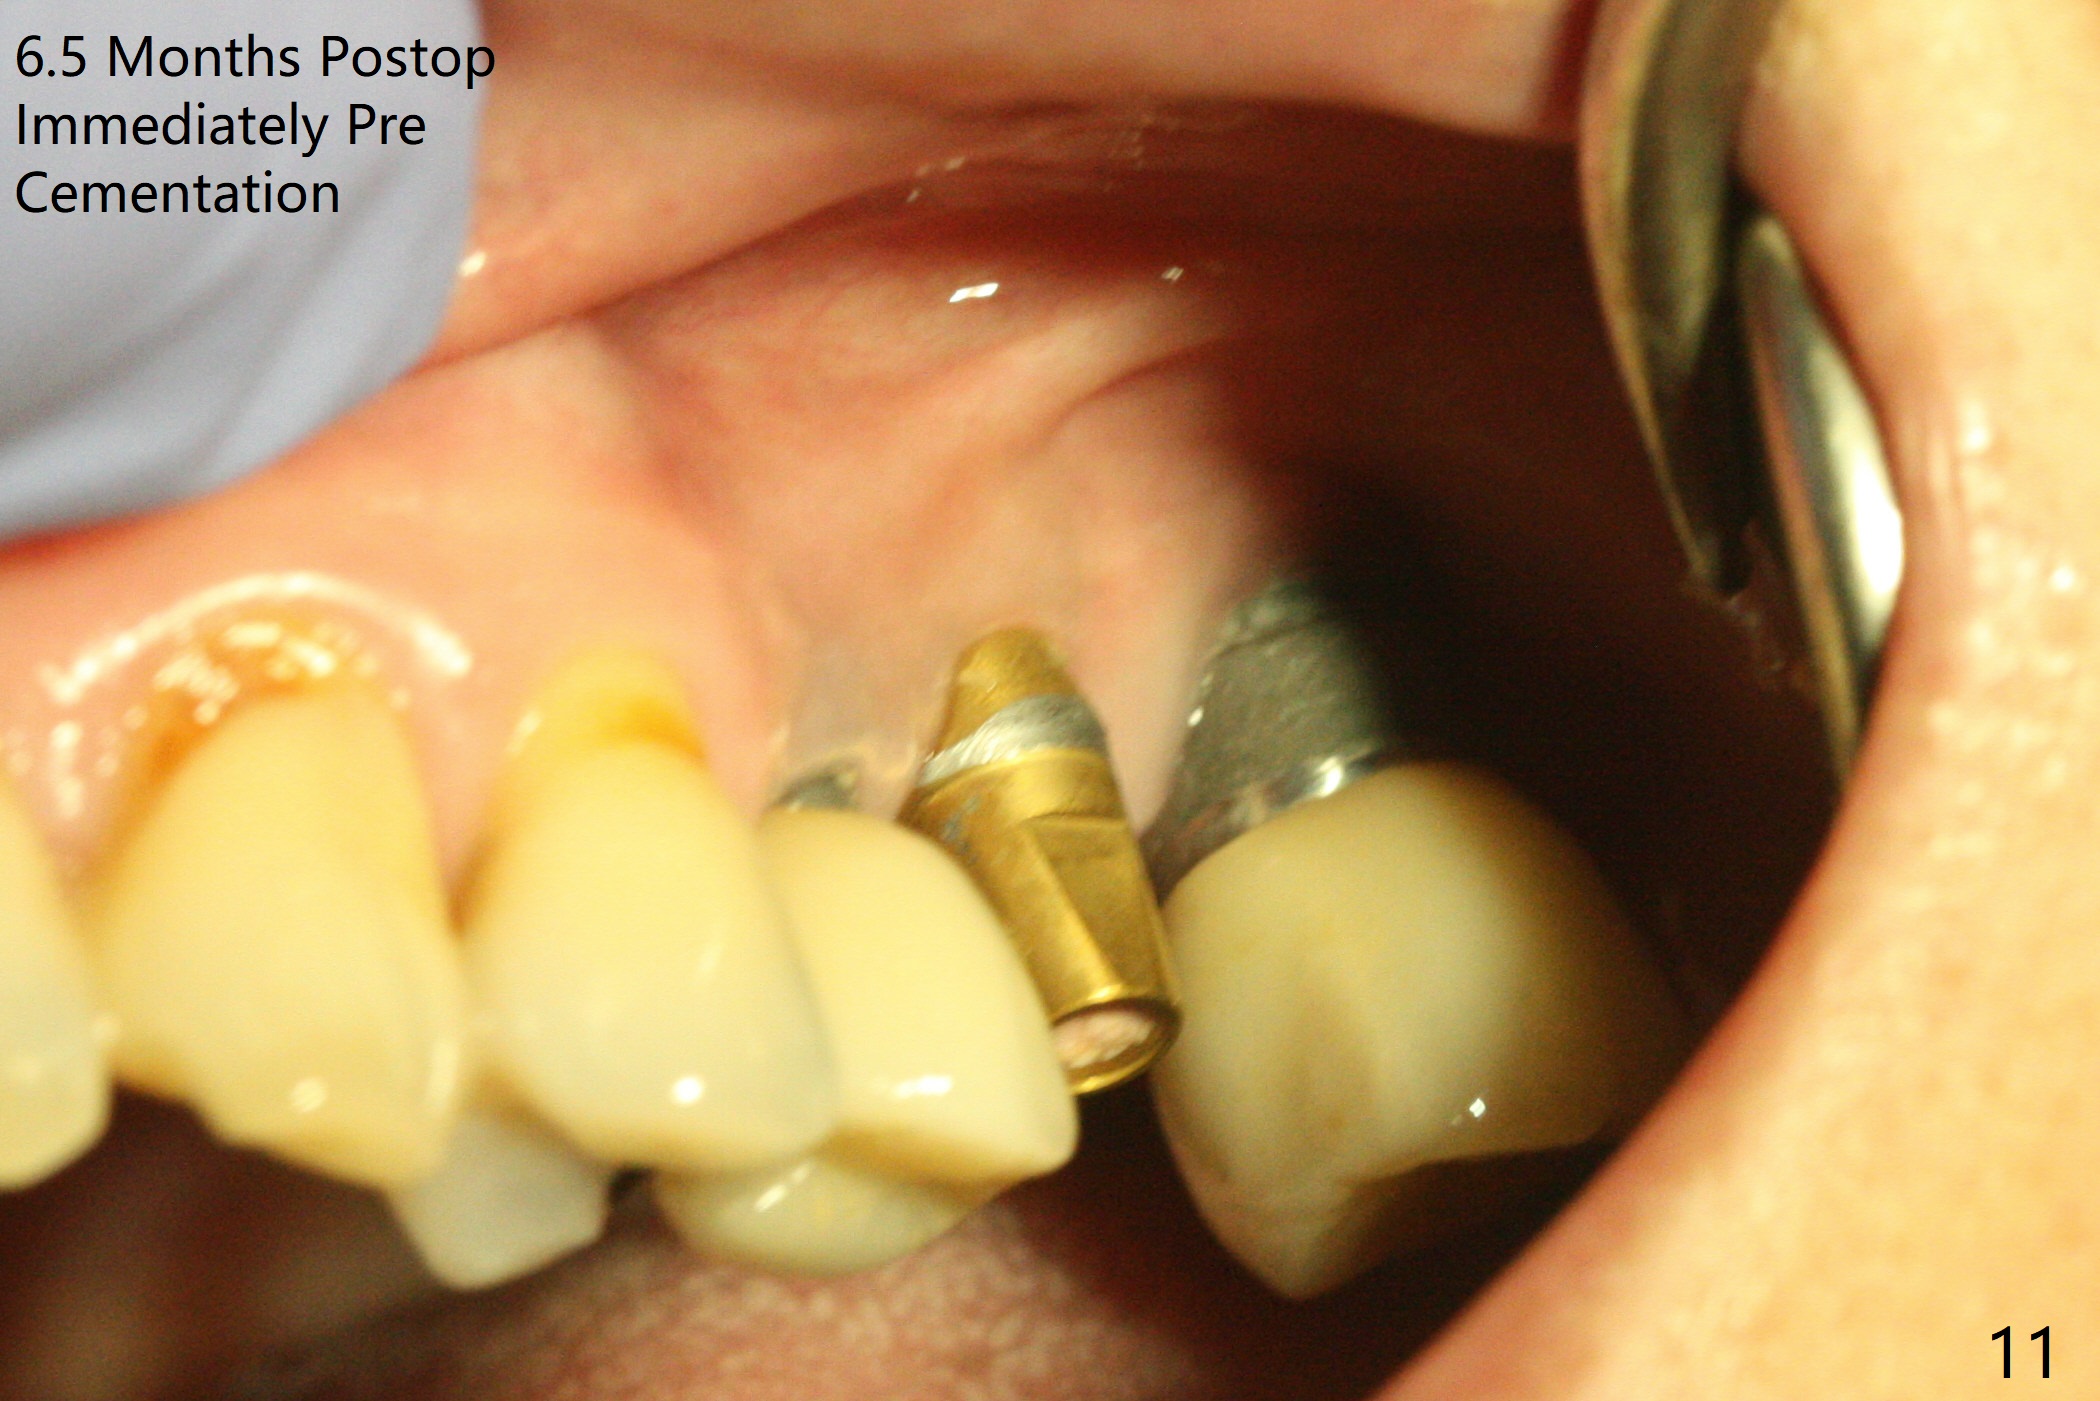

After osteotomy with guide and 2.2 mm drill for ~ 4 mm at #14, a bone expander (1.3/2.3 mm) is used free hand for sinus lift for 12 mm (from the gingival margin, Fig.1; a 10 mm long implant is planned). Following the next expander (1.7/3.1 mm) for the same depth with binding, the sinus membrane is suspected to have perforated. A piece of Osteogen Plug is inserted into the osteotomy as deep as possible with the purpose to repair the sinus membrane (no bone graft being used), followed by placing a 3.5x8.5 (instead of 10) mm implant with insertion torque ~ 25 Ncm (Fig.2,7-9, CT). As compared to preop CT (Fig.4-6), the previously grafted bone is lifted into the sinus by the bone expanders and the implant (Fig.7*). At the same time, the grafted bone has been condensed and pushed buccally (B) (Fig.8,9 *). A 4x6 mm healing abutment is inserted (Fig.3). There is crestal bone loss 6 months postop (Fig.10). Buccal plate atrophy involves the 3 implants in a row (Fig.11). The crown is loose 1 year 8 m post cementation (Fig.12). After proximal reduction, the crown/abutment rotates and sits down substantially (Fig.13). Since the crown is extremely long, it cannot be seated together with the abutment. The latter is seated with X-ray confirmation before proximal reduction of the crown (Fig.14).